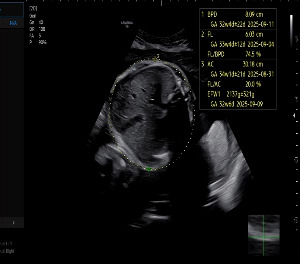

임신 32주차 4일

이제 임신도 막바지에 들어서며 정기검진 주기는 2주로 짧아졌다.

32주 차 검진에서 본 찹쌀이의 몸무게는 2.1kg. 단 2주 만에 600g이 늘어난 수치였다.

담당 선생님은 초음파 화면을 가리키며 “배둘레가 34주 아기 크기네요” 하고 웃었다.

화면 속 찹쌀이는 볼살이 한껏 올라와 있었다.

내가 장난스럽게 “볼이 너무 빵빵한데?” 하고 말하자, 마치 들은 듯 입술을 삐죽 내밀었다.

우리는 동시에 웃음을 터뜨렸다. 그 짧은 순간에도 찹쌀이가 우리와 교감하는 듯한 기분이

선생님은 다시 한번 당부했다. “양수 지수는 내려갔지만 아기가 크면 출산이 힘들 수 있어요.

KakaoTalk_20250921_205434255_01.jpg 34주차의 배둘레를 보여준 찹쌀이